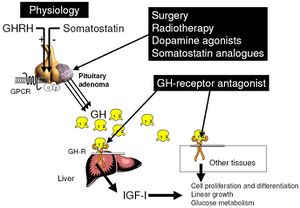

وإذا بدأ العلاج خلال فترة الطفولة يُمكن السَّيطرة على العملاقيَّة بزيادة نشاط الغدة النُّخاميَّة عن طريق العلاج بالإشْعاع. وفي بعض الحالات تزال أورام الغدَّة عن طريق الجراحة. وبإِمكان الجرَّاح أن يصل إلى الورم من خلال التجويف الأنفي، قاطعًا خلال قاع الجمجمة ليصل إِلى الغدَّة النُّخاميَّة. ولاتبدو على المريض أي آثار ندبات بعد إِجراء العملية.

Site of action of the different therapeutic tools in acromegaly. Surgery, radiotherapy, somatostatin analogues and dopamine agonists act at the level of the pituitary adenoma, while GH-receptor antagonists act in periphery by blocking the growth hormone receptor and thus impairing the effects of GH on the different tissues.